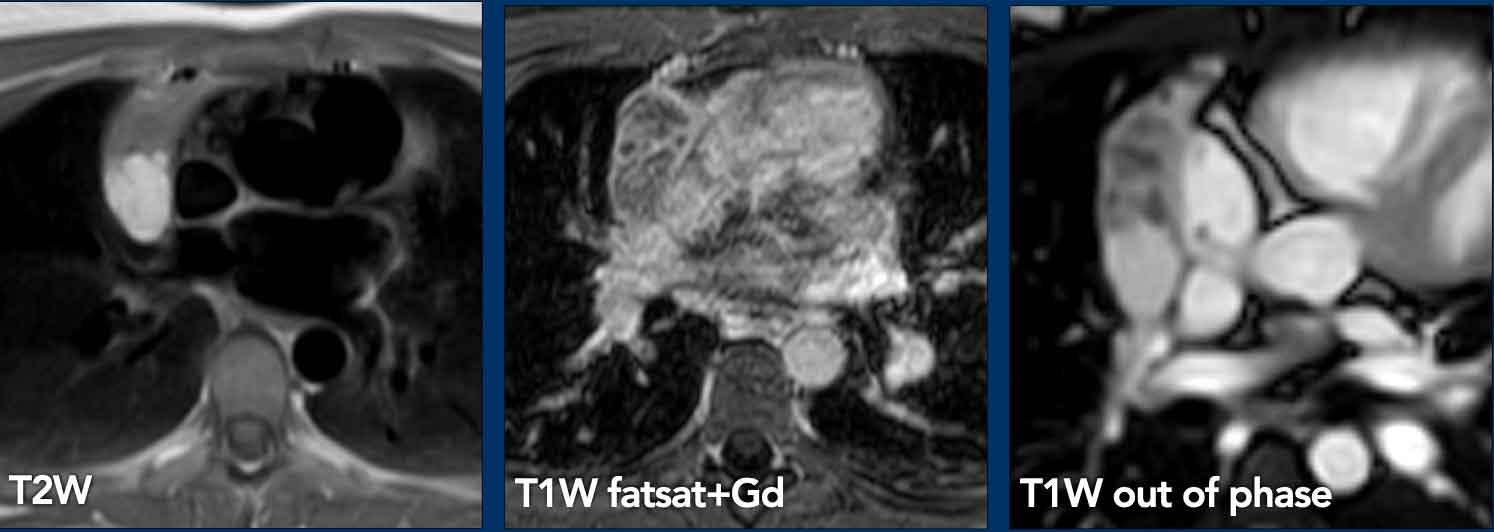

Các hình ảnh này của một nam giới 19 tuổi, được chụp CT để loại trừ thuyên tắc phổi.

Phát hiện tình cờ một khối ở khoang trước mạch máu.

Chẩn đoán có khả năng nhất là tăng sản tuyến ức và MRI được thực hiện để phân biệt thêm khối này.

Tiếp tục xem hình ảnh MRI…

Trên hình ảnh chuỗi xung T2W, tổn thương có tín hiệu tăng nhẹ.

Trên hình ảnh pha đối (out-of-phase), không có sự sụt giảm tín hiệu đáng kể.

SII nhỏ hơn 9%.

Do bệnh nhân không có bất kỳ triệu chứng nào, đặc biệt không có các triệu chứng có thể liên quan đến u lympho, và vì u tuyến ức (thymoma) là một khối u hiếm gặp, quyết định được đưa ra là theo dõi sau sáu tháng.

Tại thời điểm theo dõi sáu tháng, tuyến ức có hình ảnh bình thường.

Kết luận được đưa ra là đây là tăng sản tuyến ức hoặc mô tuyến ức tồn dư kích thước lớn, đã thoái triển trong vòng sáu tháng.